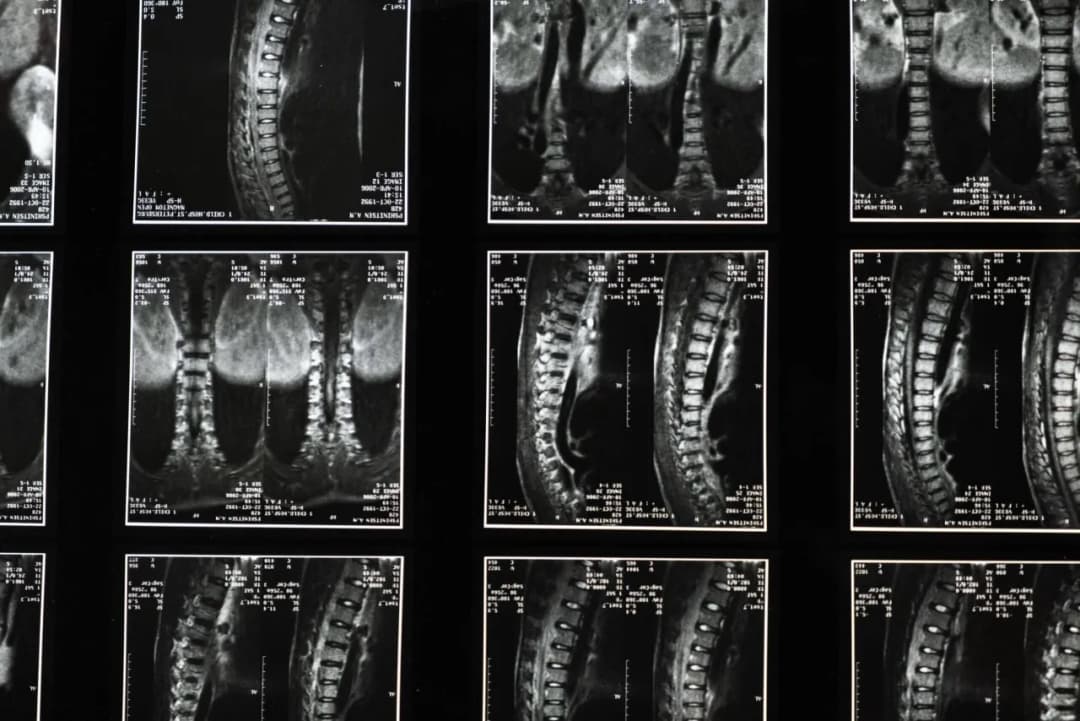

Proces diagnozy guzków Schmorla rozpoczyna się od szczegółowego wywiadu medycznego, w którym lekarz zbiera informacje na temat objawów oraz historii zdrowotnej pacjenta. Badania obrazowe odgrywają kluczową rolę w potwierdzeniu obecności guzków Schmorla. Najczęściej stosowane metody to rezonans magnetyczny (MRI) oraz rentgen (RTG). MRI pozwala na uzyskanie szczegółowego obrazu tkanek miękkich oraz struktur kręgosłupa, co jest szczególnie pomocne w ocenie guzów. Z kolei RTG jest prostszym badaniem, które może szybko wykazać zmiany w obrębie kręgosłupa.

W przypadku podejrzenia guzków Schmorla, lekarz może również zlecić dodatkowe badania, takie jak tomografia komputerowa (CT), aby uzyskać jeszcze dokładniejszy obraz. Ważne jest, aby wybrać odpowiednią metodę diagnostyczną w zależności od objawów oraz stanu pacjenta. Dzięki tym badaniom możliwe jest nie tylko potwierdzenie obecności guzków, ale także ocena ich wpływu na otaczające tkanki oraz funkcjonowanie kręgosłupa.

W przypadku podejrzenia guzków Schmorla, lekarze zalecają wykonanie kilku kluczowych badań diagnostycznych. MRI jest najczęściej rekomendowanym badaniem, ponieważ dostarcza szczegółowych informacji na temat struktury kręgosłupa i ewentualnych zmian w tkankach. RTG również jest istotne, gdyż pozwala na szybką ocenę stanu kości. Dodatkowo, w niektórych przypadkach, lekarz może zlecić tomografię komputerową, aby uzyskać bardziej szczegółowy obraz i ocenić stopień zaawansowania zmian.